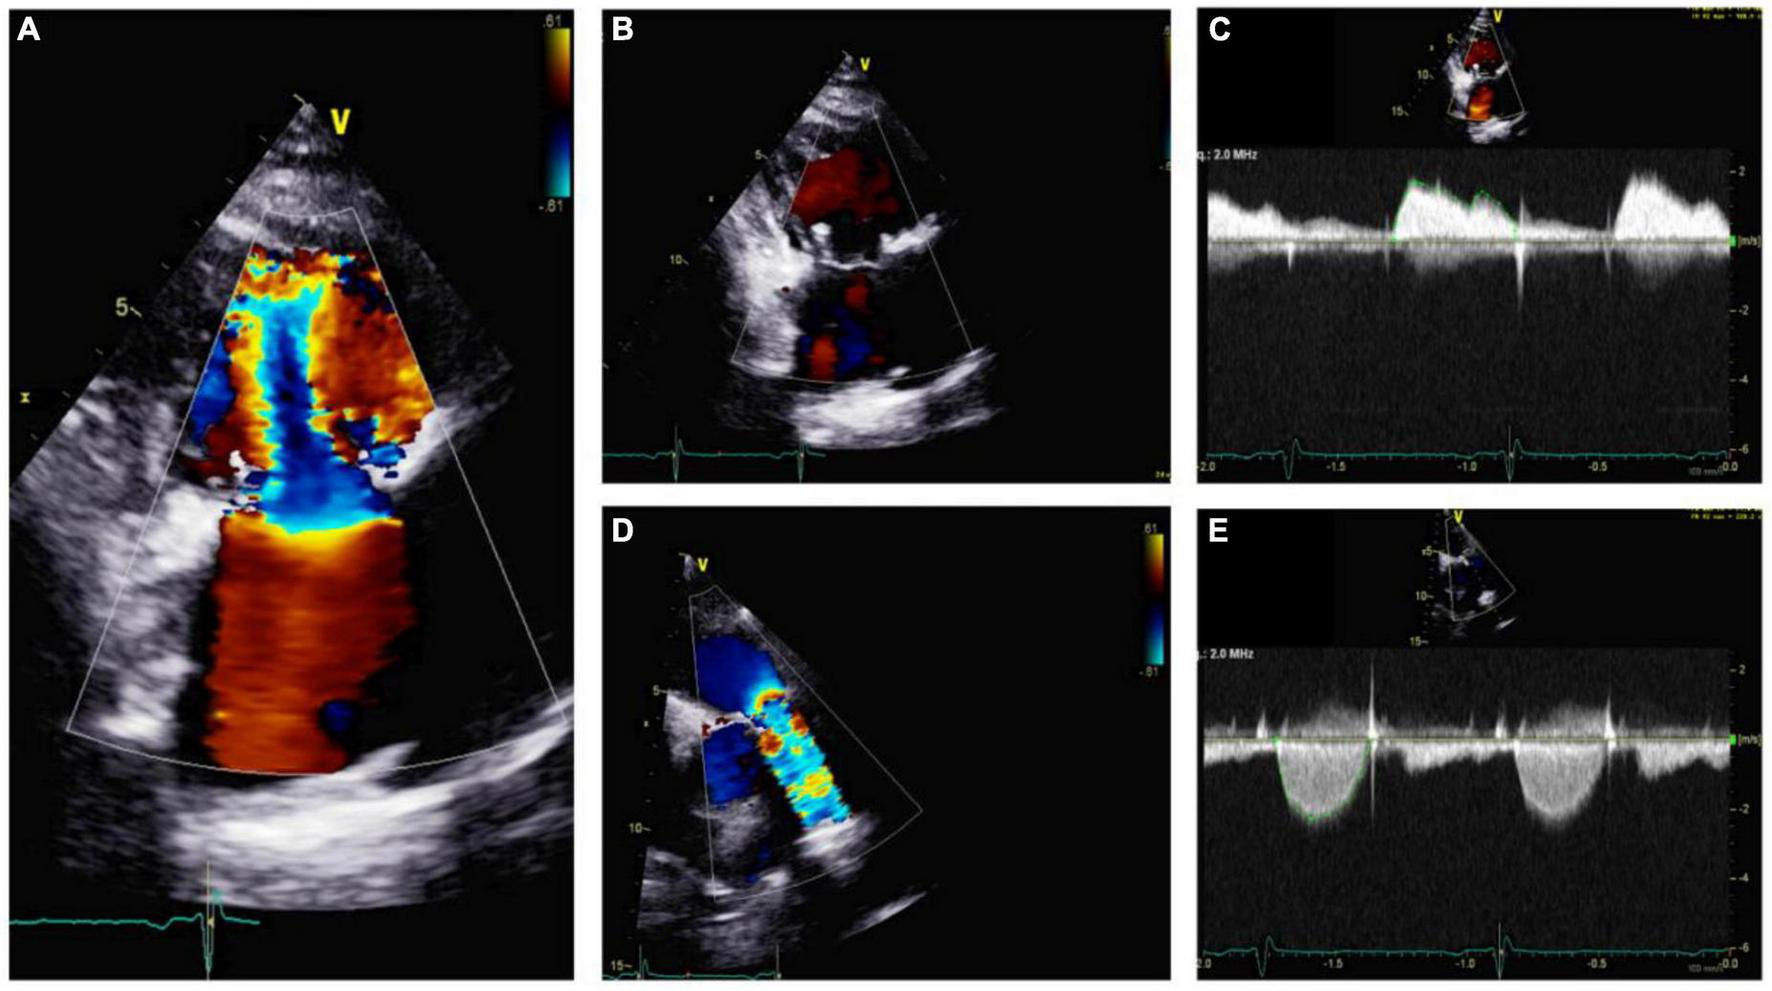

FIGURE 7

Echocardiography monitoring in carcinoid heart disease (CnHD): First follow up echo. Tricuspid valve in parasternal long axis showing mild tricuspid stenosis (A) and a lack of tricuspid regurgitation (B); continuous wave color Doppler shown (C). Pulmonic valve is shown in color Doppler (D) and continuous wave color Doppler, where there is evidence of increased pulmonary valve velocity (E).